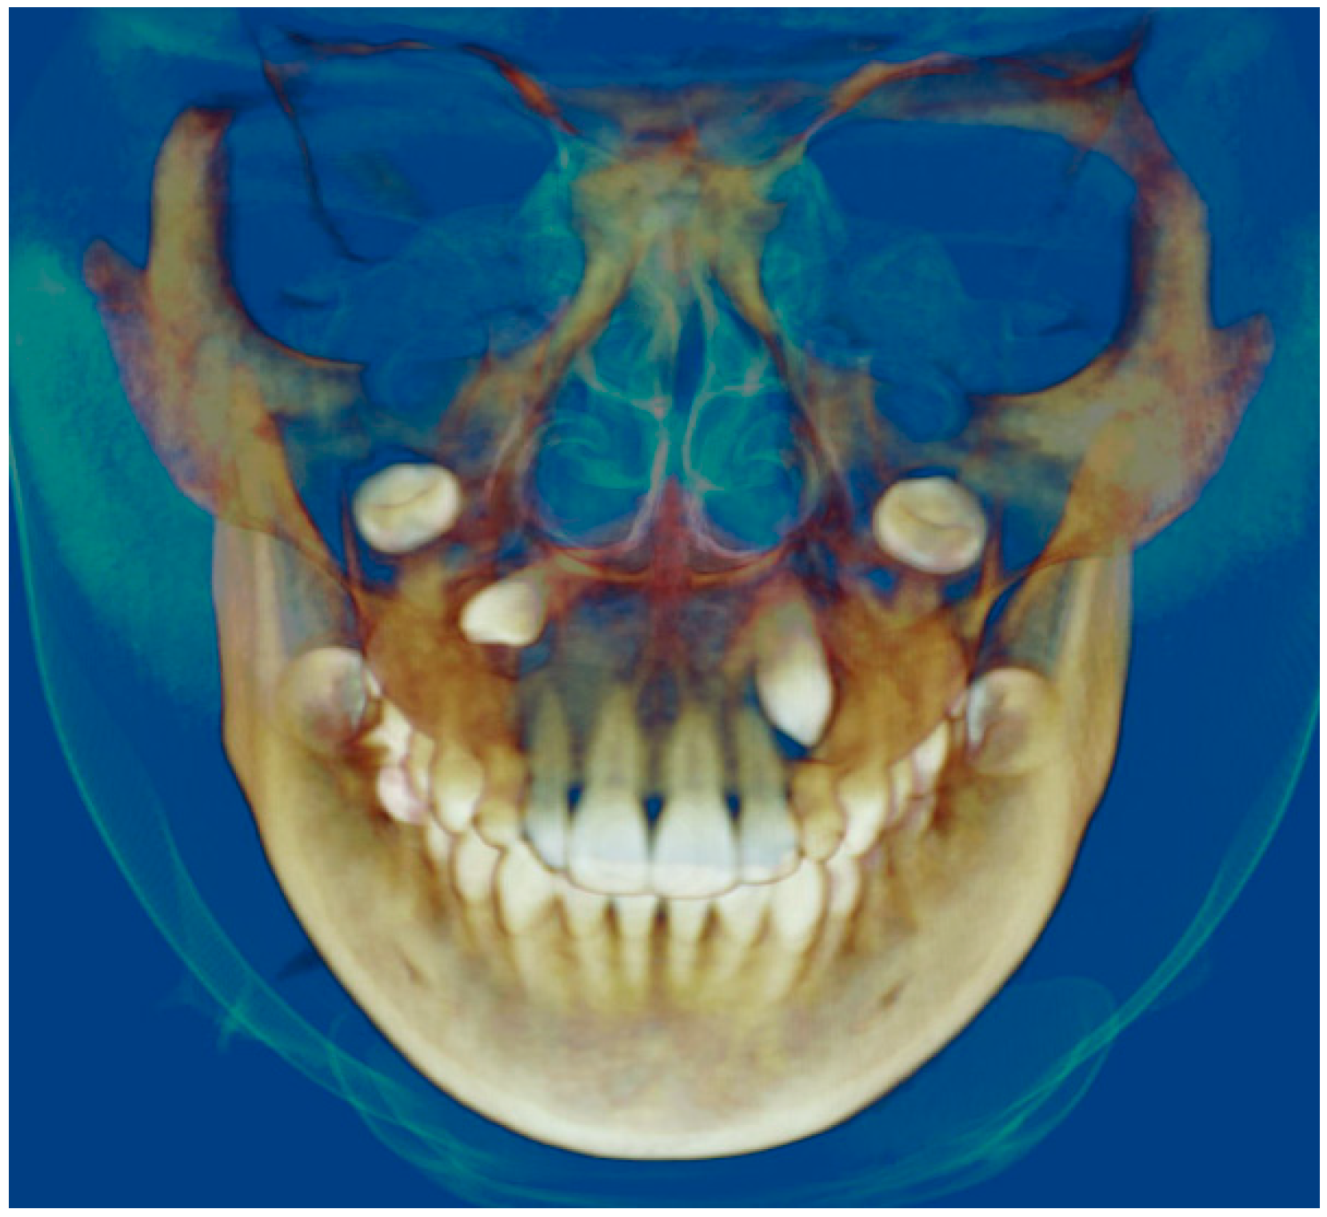

- Assessment of proposed sites of temporary anchorage device (TAD). Figure 11, Figure 12, Figure 13 and Figure 14 show correction of the Class II molar relationship using a temporary anchorage device. Figure 11 shows a pre-treatment intraoral photograph of the right side. The Class II molar relationship can be observed. Figure 12 shows coronal, sagittal and axial views, as well as a volume rendering of CBCT that was acquired in order to assess the site of the temporary anchorage device. Figure 13 shows an intraoral photograph of the right side, in which the TAD was placed mesial to the maxillary first molar, and a power chain was attached from this TAD to a hook placed distal to the lateral incisor. Figure 14 shows a post-treatment intraoral photograph showing improvement of the Class II molar relationship after removal of all orthodontic appliances.